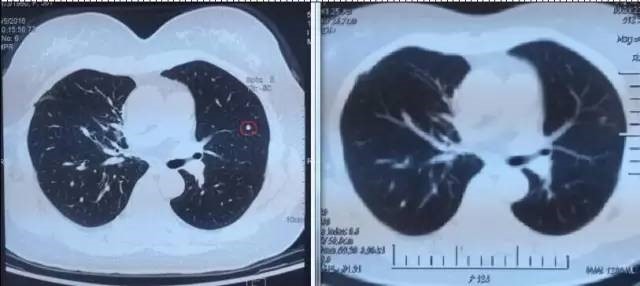

患者一年多来一直听到的都是坏消息,治疗做完后回家了,也是不放心,直到9月6日复查结果出来,肺上三个病灶消退,一年多来终于等来一个好消息,开心的不要不要的,笑容重新回到了她的脸上,先生说,现在太太每天在家开心的逗孙子玩,自己感觉体力充沛了许多,每天可以走七八千步锻炼。苏州大学附属肿瘤医院专家建议说,患者现在暂时不需要治疗了,三个月后再进行一次A45巩固治疗,增强免疫即可 。

左图红色圈内是A45治疗前三个肺癌病灶,右图为治疗后病灶消失